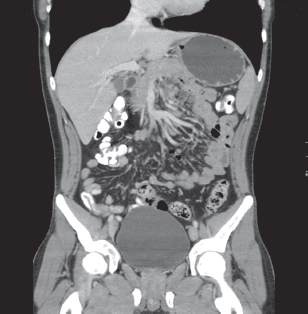

La evolución posoperatoria fue adecuada y fue dado de alta al tercer día. Posteriormente, en los controles por la consulta externa, fue valorado por el Servicio de Hematología y con los exámenes de laboratorio se descartó cualquier trastorno de la coagulación. Igualmente, se indicó una tomografía axial abdomino-pélvica contrastada, que descartó otro tipo de alteraciones (figuras 1 y 2). Se hizo seguimiento médico hasta el cuarto mes posoperatorio, observándose una adecuada evolución.

Figura 1. Tomografía axial computadorizada, realizada en el posoperatorio, descartándose alteraciones anatómicas.[/enc_su_column]

Figura 2. Escanografía abdominopélvica, en que se descartan alteraciones vasculares.[/enc_su_column]